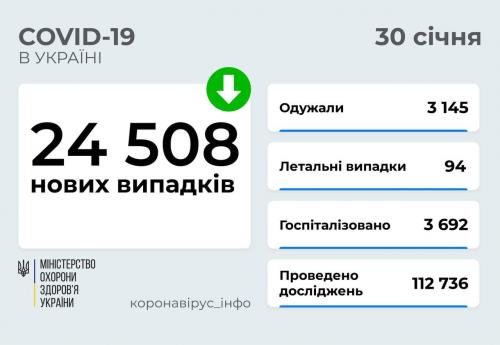

МОЗ: Уперше з початку пандемії було зроблено понад 100 тисяч ПЛР-досліджень за добу